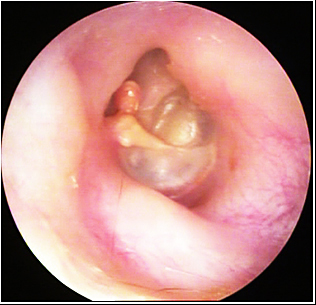

JFC Otitis media supurativa crónica. Colesteatoma.

JFC Otitis media crónica colesteatomatosa.